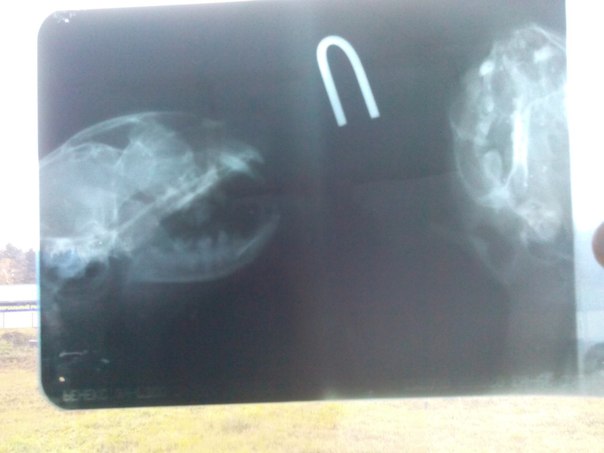

Не так давно я размещала объявление о поиске дома для кошечки инвалида Муси, даже нашли ручки готовые забрать Мусю во Владимир, но случилась беда, Муся убежала с передержки и её подрали собаки!!! Так как кошечка жила во временном доме в г. Александров, одним из кураторов было принято решение везти кошку на рентген и осмотр в Сергеев Пасад. После снимка врач рекомендовал ехать в Москву, т.к. Необходимо установка какой то пластины ( плохо поняла по телефону). Проблема в том что мы были совсем не готовы к таким проблемам, нам очень необходима поддержка в том числе и финансовая!!! Эльвира сейчас едет с Мусей в Москву, но денег на операцию нет!!!

Кошечка Муся перелом челюсти!!! Срочно нужна операция!!!

фото